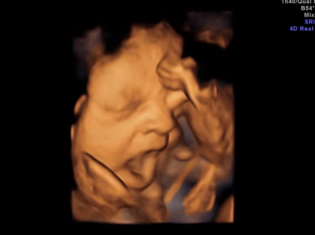

The study that determined babies yawn was led by Nadja Reissland, DPhil, from the Department of Psychology in the University of Durham in the United Kingdom. The researchers scanned 15 healthy babies while still in the mother's womb using 4D ultrasound technology. The ultrasounds were done at 24, 28, 32 and 36 weeks of pregnancy.

The researchers watched how the babies opened their mouths on the scans at each stage of development. They wanted to compare simple mouth openings with true yawns. The researchers measured how long it took for the babies' mouths to reach the point where they were open the widest.

If the babies spent more than 50 percent of the the time their mouths were open to open it to the widest point, the researchers classified that as a yawn. They also looked at whether the number of times the babies yawned changed over time. They found that the babies yawned less and less after the 28th week of pregnancy.